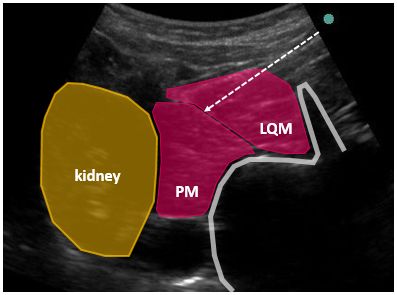

QLB-3はtransmuscular approachです。

つまり腰方形筋を突き破って、筋肉の向こう側に注入します。

ブロックするときの体位は、側臥位とし

コンベックスプローブを

腰神経叢ブロックshamrock approachのように置くと良いでしょう。

さらに、プローブを若干頭側にスライドさせ

腎臓が見えるポジションで行うのがQLB-3のプロトタイプです。

図のように、腰方形筋を貫き

大腰筋の手前もしくは腎臓の手前を狙います。

もちろん、腰方形筋の向こう側にあるtransversalis fasciaは貫かずに、その筋膜内に注入します。